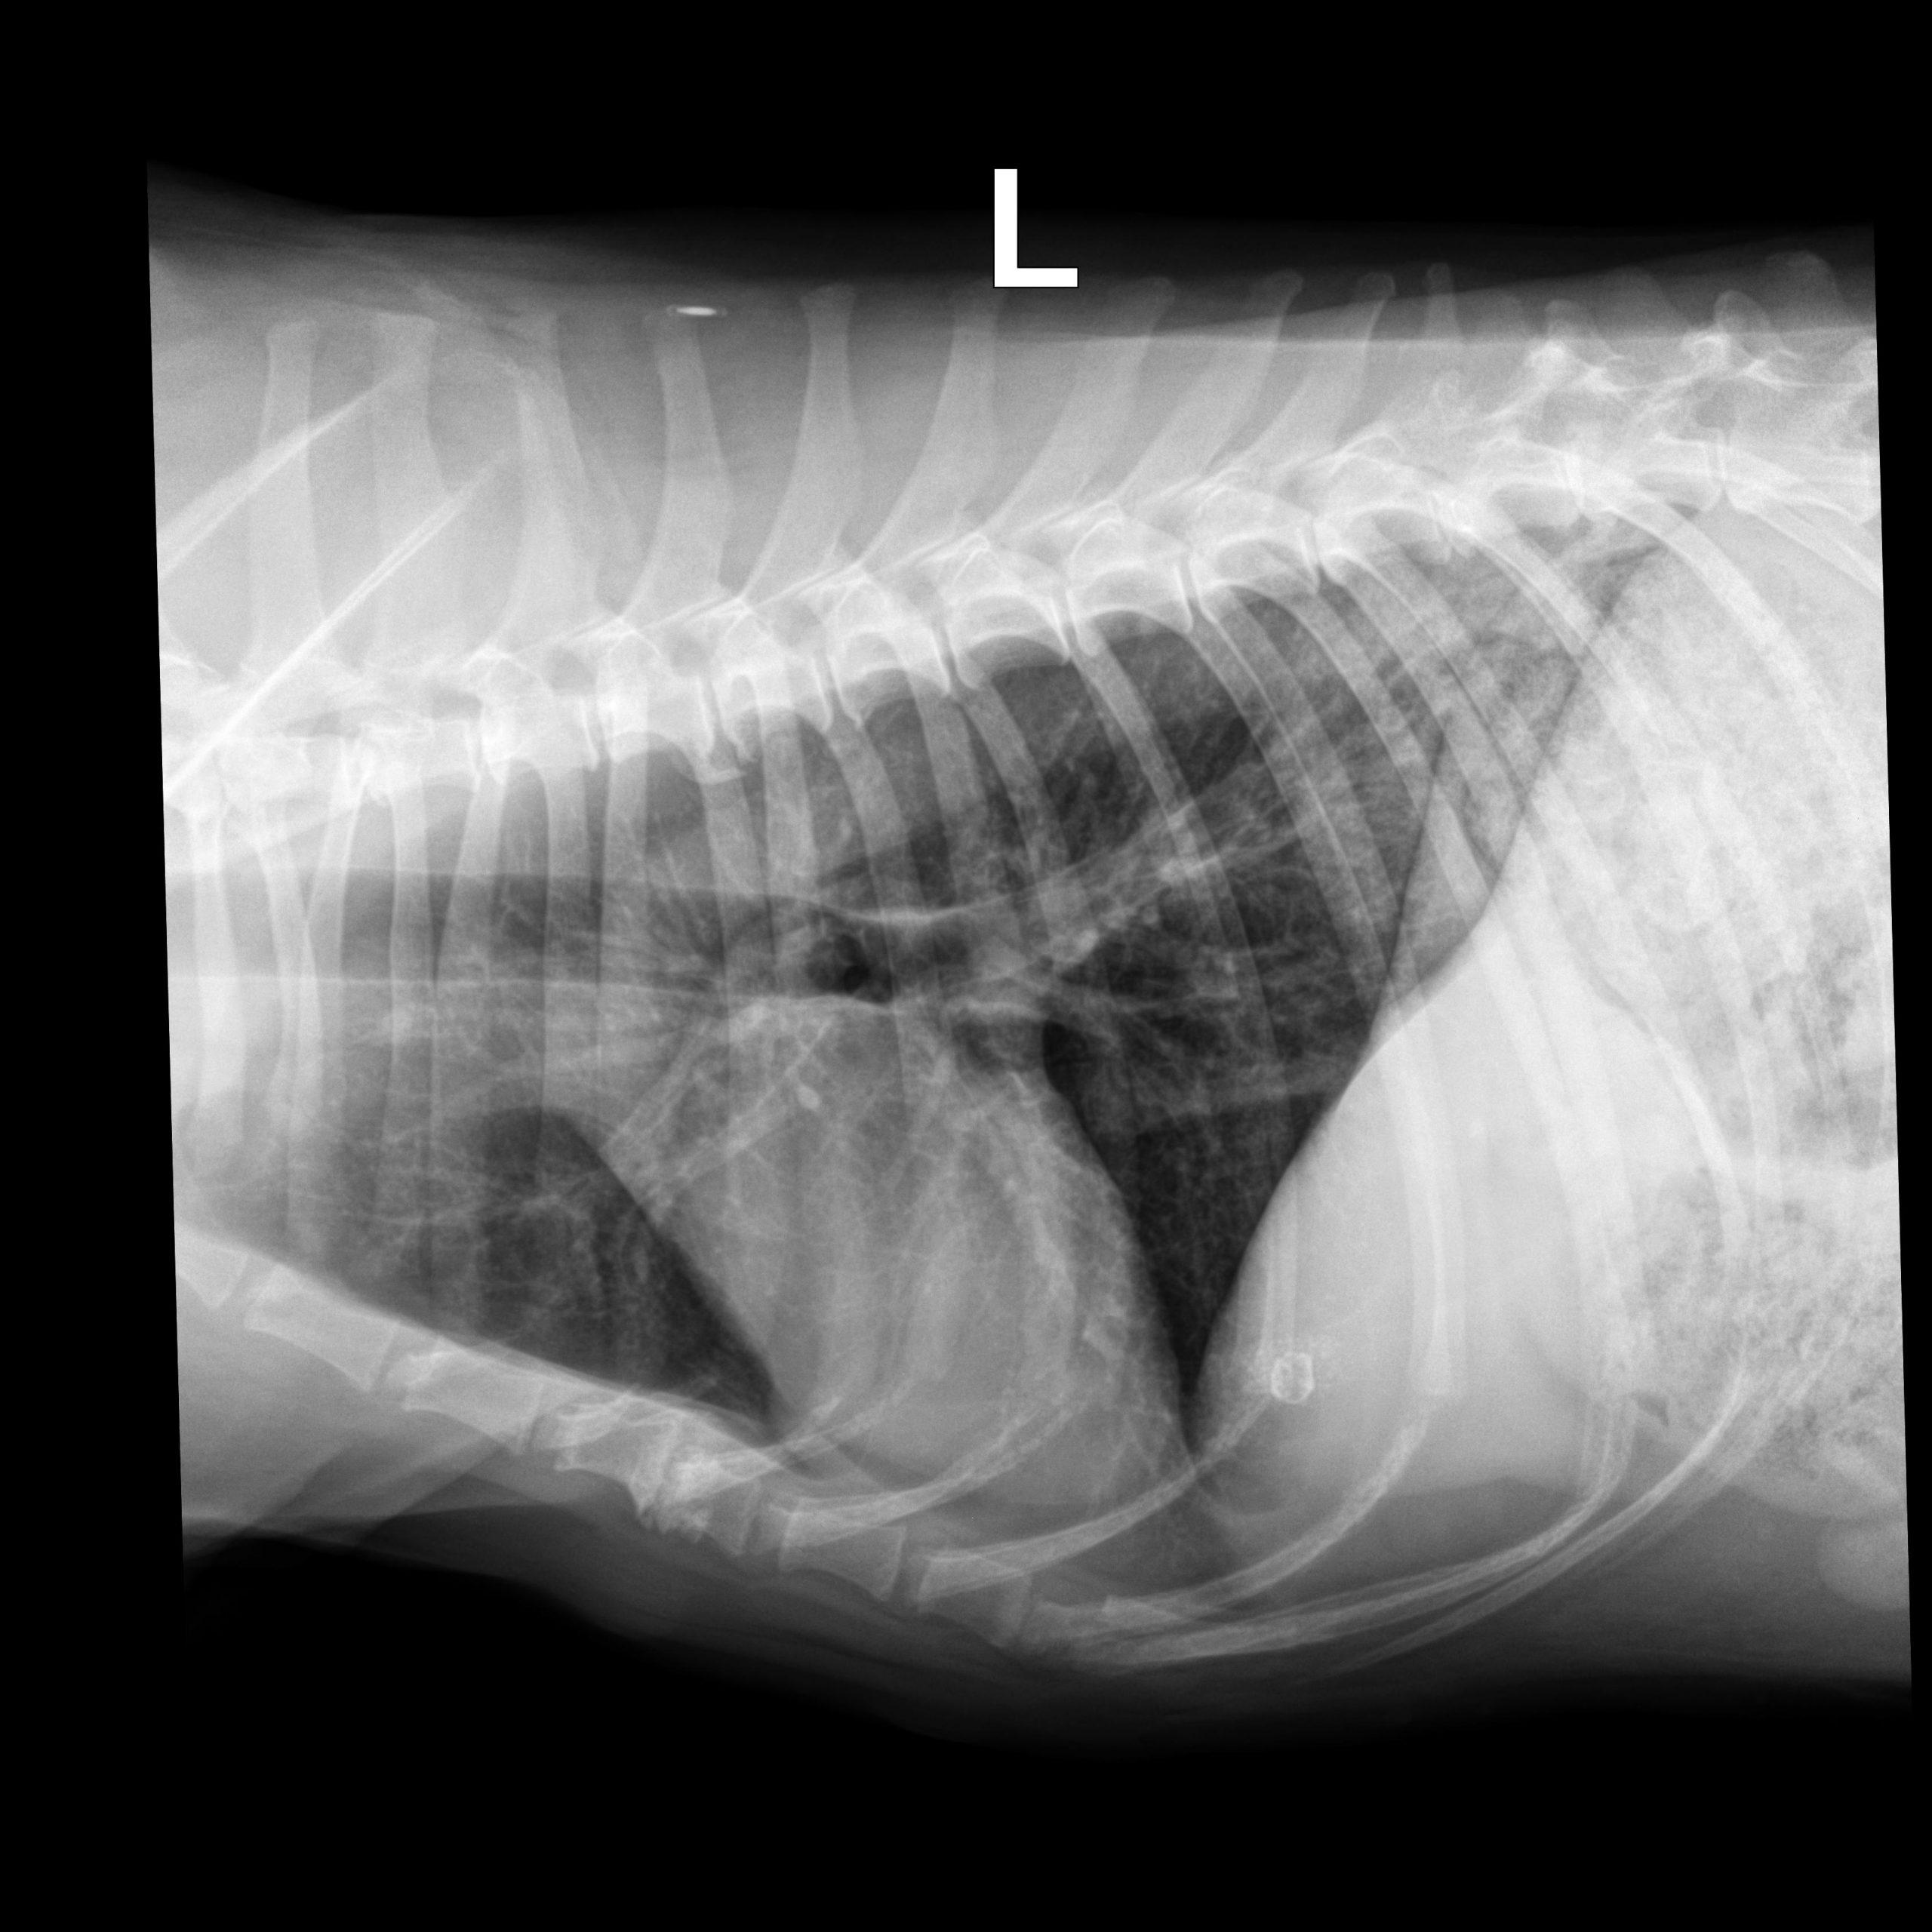

Rads of right lateral, left lateral and VD thorax – Osseous structures: There was mild ventral vertebral endplate modeling within the

mid thoracic spine consistent with spondylosis deformans.

Intrathoracic structures: The course of the trachea was normal. The cardiac silhouette

was small, the caudal vena cava and the pulmonary vasculature were thin.

There was an area of diffusely increased interstitial opacity within the caudodorsal

aspect of the lung.

There also was a generalized bronchial pattern with increased wall visibility and

mineralization.

There was a small soft tissue opaque nodule associated with the cranial lobar vessels

best visible on the left lateral view (see image below)

The findings indicate mild non-cardiogenic (consider neurogenic) pulmonary edema. There was hypovolemia with microcardia and underperfusion of the lung and a chronic bronchial pattern, which may be age related or associated with chronic airway disease. The small nodule is compatible with an end on pulmonary vessel. A secondary neoplastic nodule cannot be ruled out. The mineral opaque material is likely associated with the hepatic biliary system. This is usually benign. Correlate with the chem profile.